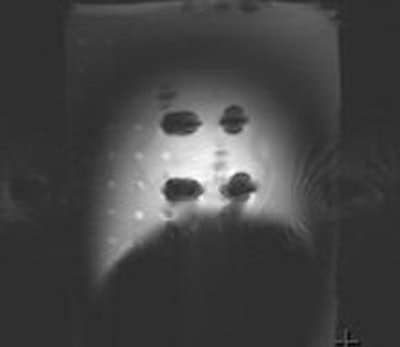

![]() |

| Above, experimental setup for evaluating MR-imaging related artifacts at 3-tesla includes five representative bullets placed on a plastic frame. The top four are conventional bullets, and the bottom bullet is the armor-piercing bullet containing a steel core. Below, MR-imaging induced artifact observed for the five bullets reveals excessive signal void associated with the armor-piercing bullet (No. 32) at the bottom of the image. |